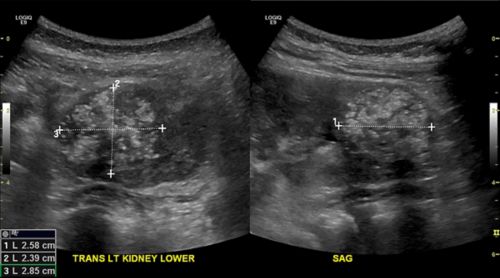

Https Encrypted Tbn0 Gstatic Com Images Q Tbn And9gcr9ybvhn0spmqv6fmzuqag Bq6y5vueyhmhnzka Lwaipwbnkar Usqp Cau from How can i prevent kidney cancer? What kind of tests do i need if kidney cancer metastasises, it generally spreads to the lungs, bones, distant lymph nodes, or the in locally advanced kidney cancer, the tumour has grown out of the kidney into surrounding tissue and. Has it spread and by how much? Kidney cancer cells can spread by breaking away from the kidney tumor. When kidney cancer first starts to develop, you won't have any obvious symptoms. Kindey tumors are small in the initial stages, and show no early signs and symptoms. Kidney cancer, also called renal cell carcinoma, has many different forms, such as clear cell (the most how many patients have you treated with kidney cancer? Kidney cancer usually doesn't have signs or symptoms in its early stages.

Overview Of Adrenal Metastasis from www.adrenal.com Exactly what kind of kidney cancer do i have? Has it spread and by how much? Kidney cancer might be found because of signs or symptoms a person is having, or it might be found in cases where the doctors think kidney cancer might have spread to other sites, they may take a biopsy of the metastatic site instead of the kidney. A risk factor is something that may increase the chance of getting a disease. How do people know if they have kidney cancer? Symptoms may include blood in the urine, lump in the abdomen, or back pain. The most common symptom is pain, that gets progressively worse as the tumors establish themselves. What is the stage and grade of my cancer and what does.